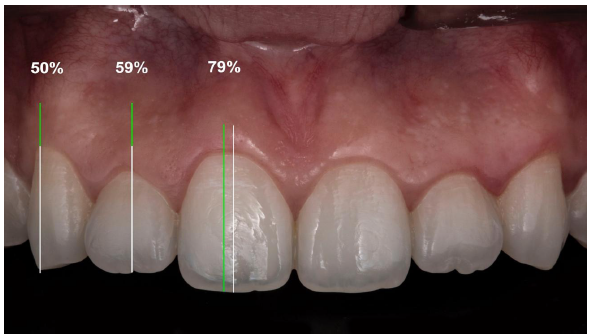

Al análisis de los modelos de estudio se encontró que el cénit gingival del incisivo central se ubicaba en un 72,8% de la muestra hacia distal del eje longitudinal de la pieza observada, mientras que, en los incisivos laterales se ubícaba en el 59,2% de la muestra, el cénit gingival se encontraba sobre el eje longitudinal del diente, al igual que en el 50,5% de los caninos (tabla 1 y figura 1), pero no se encontró relación entre la ubicación del cénit gingival y el género (tabla 2).

Al cuantificar la distancia en el que se ubica el cenit con respecto al eje longitudinal, se encontró que fue de 0,54 mm hacia distal en incisivos centrales (tabla 3), y 0 mm en los incisivos laterales y caninos superiores (figura 2). No se encontró relación entre la distancia del cénit al eje longitudinal con el género (tabla 4) y, asimismo, con el grupo etario (tabla 5).

Al relacionar la morfología dental y el cénit gingival, se obtuvo que, en los incisivos centrales superiores el cénit gingival se ubicó hacia distal en todos los tipos de morfología dental hallados; mientras que en los incisivos laterales superiores, éste se hallaba sobre el eje longitudinal en las piezas cuadradas y ovales, en cambio se ubicaba hacia distal en piezas triangulares, de igual manera ocurrió en los caninos superiores (tabla 7).